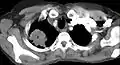

CT scan showing a Pancoast tumor (labeled as P, non-small cell lung carcinoma, left lung), from a 47-year-old female smoker

CT scan showing a Pancoast tumor (labeled as P, non-small cell lung carcinoma, left lung), from a 47-year-old female smoker